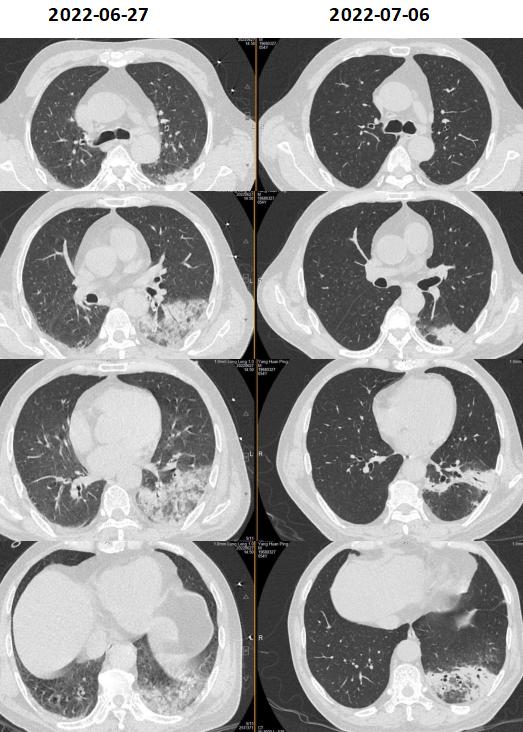

患者6.29、6.30仍反复高热,热峰39℃以上,复查感染指标PCT及CRP下降,但临床症状改善不显著,仍反复高热。 气促症状无好转,查床边胸片提示病灶范围较前明显增加。 追问病史, 患者曾在地下车库扫水 ,入院前至今反复有腹泻、解稀烂便或水样便3-4次/日。

治疗后患者湿罗音减少,左肺可闻及Velcro啰音,7-6复查胸部CT如下:

考虑感染继发机化性肺炎,7.6加用泼尼松30mg po qd治疗机化性肺炎,继续多西环素0.1g bid治疗军团菌肺炎,并办理出院。

该患者的另一个临床特征是高PCT水平,据文献报道高PCT水平与需ICU治疗和高死亡率相关。 我们注意到,在病程中,PCT水平与体温未成平行下降关系,可能的原因为: 患者在入院初存在胃肠道症状和体征,包括腹泻、肠鸣音亢进。肠道作为细菌的蓄水池,此类患者可能存在肠道菌群移位。虽然没有相应的文献支持,我们在明确病原体为军团菌后,仍然将美平保留到7月2日,与多西环素重叠使用3天,直至PCT下降到安全范围。尽管在多西环素介入后, 6月30日床边胸片提示病灶较前明显增多,左肺大片浸润影,考虑到患者重症肺炎以及多个死亡相关预后因素存在,加用利福平5天联合抗军团菌。 患者在有效抗感染治疗基础上,7月6日复查胸部CT提示机化表现 ,氧合改善欠佳,给予短程激素应用,7月14日复查胸片提示病灶显著吸收。1个月后电话随访,患者原有咳嗽、气促等症状消失。